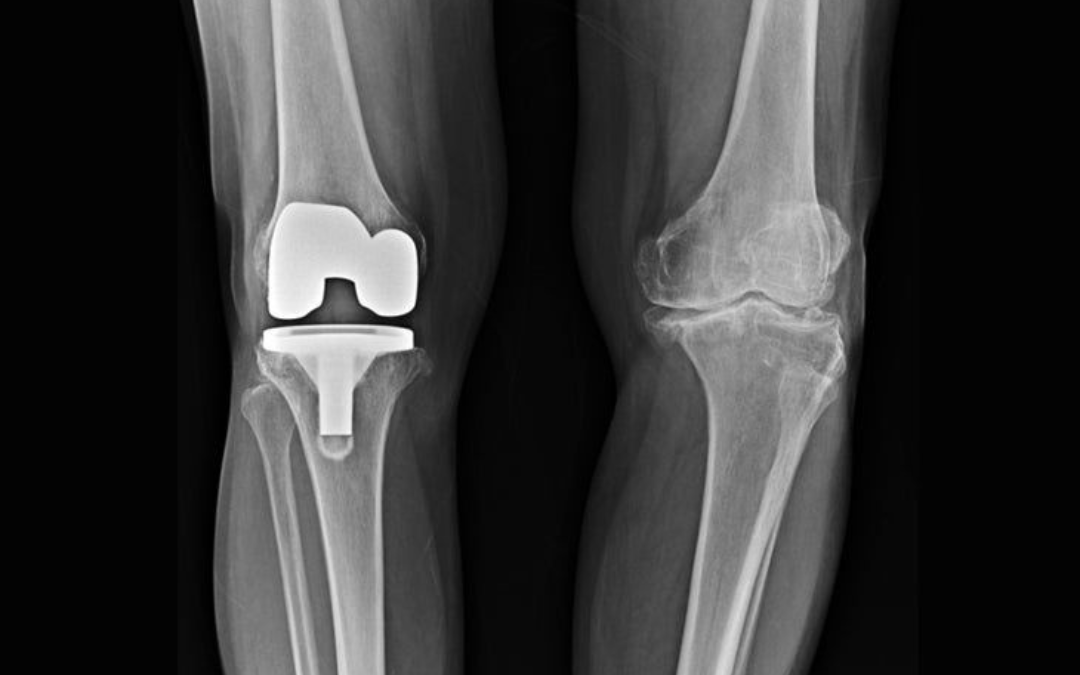

Regain Mobility with Expert Total Knee Replacement